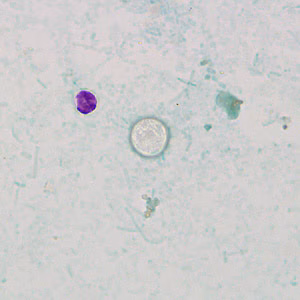

A 29-year-old woman had complaints of abdominal cramping and diarrhea that had been persisting for 5 days. She went to a local clinic to determine what was causing her illness. A stool specimen was collected in formalin and sent to the State Public Health Laboratory for routine ova-and-parasite (O&P) examination. A wet mount preparation was made after concentrating the specimen and was examined. The technician noticed suspicious round objects and suggested that a Kinyoun’s modified acid-fast stain be performed. Figures A–C show what was found on the acid-fast stained fecal smear. What is your diagnosis? Based on what criteria?

Figure A